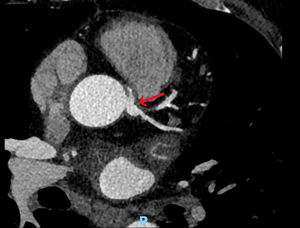

In April 2020, the patient presented with dizziness, instability, dyspnea and worsening angina, rising suspicion for acute coronary syndrome. Sinus rhythm and left ventricular hypertrophy were observed on ECG. Two stress tests, both of which had to be halted due to angina and dyspnea, were electrically negative for ischemia. A coronary computed tomography angiography presented similar findings (Fig. 2), yet a PET scan showed possible inferior ischemia.